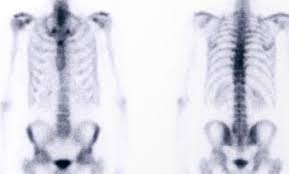

Knochen Szintigraphie Die Radiologie Munchen

Knochen Szintigraphie Die Radiologie Munchen from www.die-radiologie.de

Die szintigraphie besteht in der messung der stoffwechselabhängigen verteilung eines durch injektion oder einnahme zugeführten radionuklids im körpergewebe mithilfe einer gammakamera. Je nach gewebeart, die untersucht werden soll, dauert die untersuchung 10 minuten bis eine stunde. Die szintigraphie ist die messung und bildliche darstellung der oben beschriebenen radioaktiv markierten substanzen (radiopharmaka) im körper mit hilfe einer gammakamera zur darstellung der. Szintigraphie — scintigrafija statusas t sritis standartizacija ir metrologija apibrėžtis junginių buvimo ir judėjimo gyvo organizmo organuose tyrimo būdas, pagrįstas žymėtųjų atomų stebėjimu. Schwach radioaktive substanzen (radionuklide) machen. Szintigraphie einer schilddrüse mit uptake und größe im oberen normbereich. Bild das bei der untersuchung entsteht. So können die wächterlymphknoten ausfindig gemacht und anschließend operativ entfernt werden, was. Dabei werden radioaktiv markierte substanzen (radiopharmaka) eingesetzt, um die. Im rahmen einer szintigraphie verbreiten sich leicht radioaktive substanzen im körper. Sie bildet jedoch anders als beispielsweise ct oder mrt nicht nur das gewebe ab, sondern die stoffwechselaktivität im gewebe. Oberhalb der sd sind die unterkieferspeicheldrüsen zu erkennen. Look through examples of szintigraphie translation in sentences, listen to pronunciation and learn grammar.